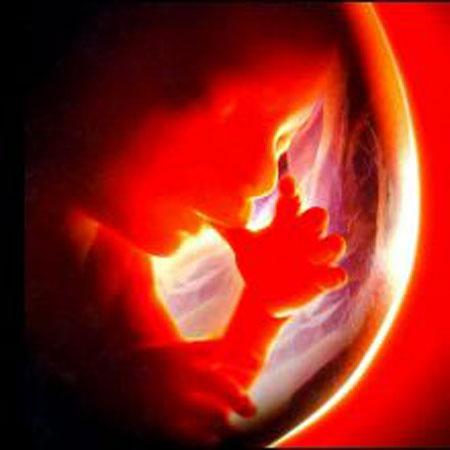

Зачатый ребёнок - невинное существо. Эмбрион - наиболее слабое и беззащитное существо из всех человеческих существ. По божественной мудрости он предоставлен заботам других людей и, особенно, заботам матери. У него нет никаких возможностей защищаться. Даже у маньяков-серийных убийц есть адвокаты в суде.

Этот метод достаточно стандартен до момента отсечения пуповины. При Кесаревом сечении отсасывается слизь ребёнка и ему оказывается интенсивная терапия в инкубаторе для новорождённых, где делается всё для его выживания. На этом снимке вы видите ребёнка весом 900 грамм, после 24-х недельной беременности, который был абортирован. Отсечённый от пуповины, он был положен в ведро и оставлен умирать, а после выброшен в печь. Я думаю, будет уместно вспомнить Клятву Гиппократа. Как врач может смотреть на смерть ребёнка?!Аборт с помощью отравления солью

© REUTERS/Baptist Health South Florida

Март. Амилия Соня Тейлор – самый маленький недоношенный ребенок, который выжил после родов.